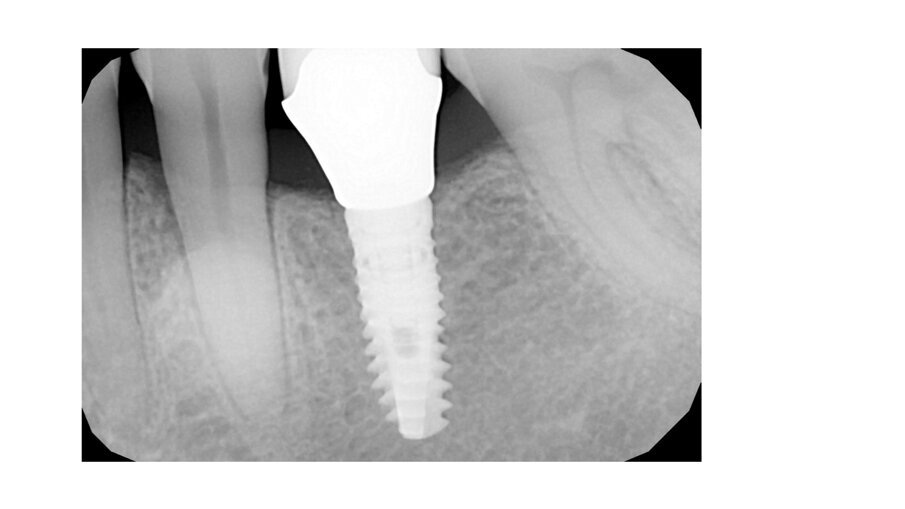

During daily practice, it is very common to face situations where the implant has to be placed lingually due to normal resorption (Fig. 1) of the buccal plate after the extraction. But, at the same time, it is not necessary to perform bone grafting procedures. The result of this scenario is to increase the stress on the implant-bone complex when we use rigid materials like conventional ceramics (Fig. 2). For this daily practice situation, the combination of rigid and resilient materials against the antagonist, allows the stress to the implant-bone complex to be reduced (Figs. 3, 4).

Fig. 1: Implant placed lingually due to the normal resorption of the buccal plate.

Fig. 2: The design of the crown has to be with a pseudo pontic, increasing the oblique load on the crown.